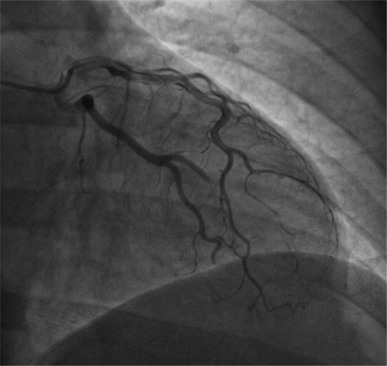

We present a case of a 48-year-old man with an atypical type 2 myocardial infarction (MI)/myocardial infarction with nonobstructive coronary arteries, caused by a coronary embolism originating from the inferior vena cava and passing through a patent foramen ovale (PFO). The patient presented to the emergency department with oppressive retrosternal chest pain. His medical history included papillary renal cell carcinoma and seminoma with recent abdominal lymph node recurrence. The electrocardiogram indicated an inferolateral ST-segment elevation (STE), prompting emergency coronary angiography, that revealed distal occlusion of the circumflex artery and the obtuse marginal branch, suggesting an embolic etiology. Stent placement was deferred, and the management approach involved thromboaspiration and unfractionated heparin infusion. Abdominal imaging identified a thrombotic formation in the inferior vena cava and a transesophageal echocardiogram revealed a PFO with a right-to-left shunt, supporting the diagnosis of a paradoxical embolism. Follow-up coronary angiography showed vessel patency, and the patient was then treated with low-molecular-weight heparin. This case underscores the importance of considering alternative etiologies for STE myocardial infarction beyond acute plaque rupture, highlighting the need for individualized management strategies, particularly in patients with complex medical histories, and given the lack of standardized treatment guidelines for coronary embolism.